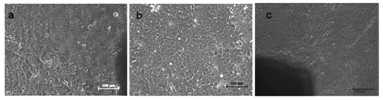

Rabbit limbal epithelial cells in culture started migrating out from explants after three days in MEM. When the media was switched to SHEM, the cells showed cobble stone morphology of epithelial cells (Figure 4).

Figure 4 Rabbit Limbal Epithelial Culture shows cobble stone shaped epithelial cells migrating from explants (a) low magnification 10X and (b) Higher magnification 20X. Figure (c) shows LESC migrating out from limbal explants.